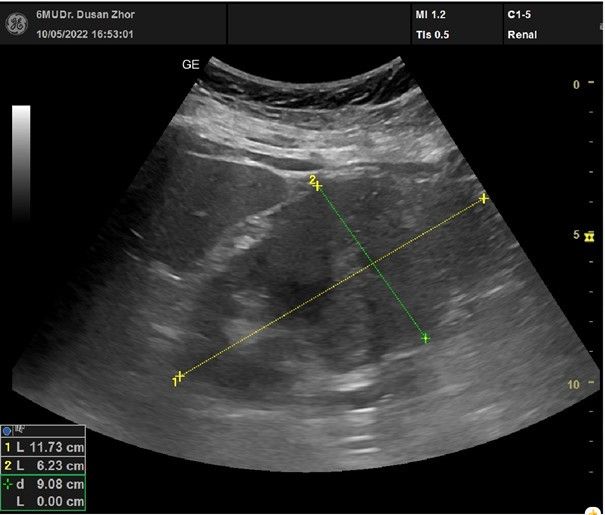

Pro přítomnost varujících příznaků, nelepšení celkového stavu pacientky, lehkou bolest v levém boku pokládáme klinickou otázku na patologii levé ledviny, jater a žlučníku. Provedené Point‑of‑Care ultrasonografické vyšetření (POCUS) jaterní krajiny a ledvin – s nálezem tří anechogenních útvarů jater charakteru cyst, žlučník nezachycen, v centrální oblasti levé ledviny útvar velikosti cca 5 cm, bez známek dilatace dutého systému (obr. 1). Stanovena pracovní diagnóza tumorózní expanze levé ledviny. Pacientka byla týž den odeslána k akutnímu urologickému vyšetření.

Obr. 1 Nález na levé ledvině u pacientky z kazuistiky zjištěný metodou POCUS (trvání vyšetření 5 minut).

POCUS – Point‑of‑Care ultrasonografické vyšetření